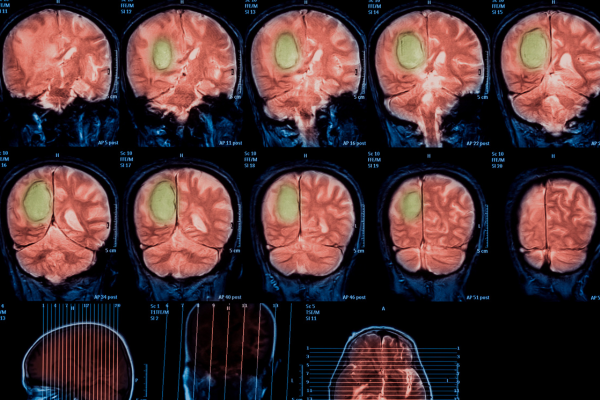

- Imaging Tests (MRI, CT Scan) – Detailed brain scans help detect tumors, their size, and location.